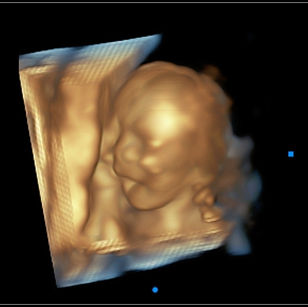

18 Weeks Pregnant

Size: ~5.5 inches (14 cm), the size of a Bell Pepper!

Development Highlights:

Baby can hear sounds and may respond.

Vernix caseosa begins forming to protect skin.

Joints more flexible; baby can bend arms and legs.

Baby may start thumb sucking.